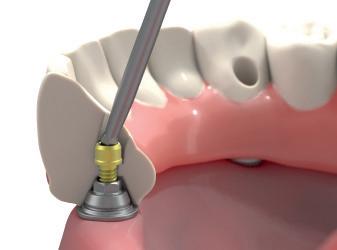

Endodontic file separation and patient safety

With World Patient Safety Day having taken place in September, Dr simon parsons, Dentolegal Consultant at Dental Protection, looks at what we can do to reduce our risk of procedural error from endodontic file separation

Patient safety is paramount in endodontic procedures, with guidelines in place to prevent infection and cross-contamination.

In addition to proper sterilisation and singleuse protocols for endodontic instruments, other strategies include the use of a rubber dam to prevent the aspiration or swallowing of instruments.

These are all essential for minimising risk in endodontic procedures. However, one of the most frequent adverse events reported is the separation (or fracture) of an endodontic instrument within a tooth.